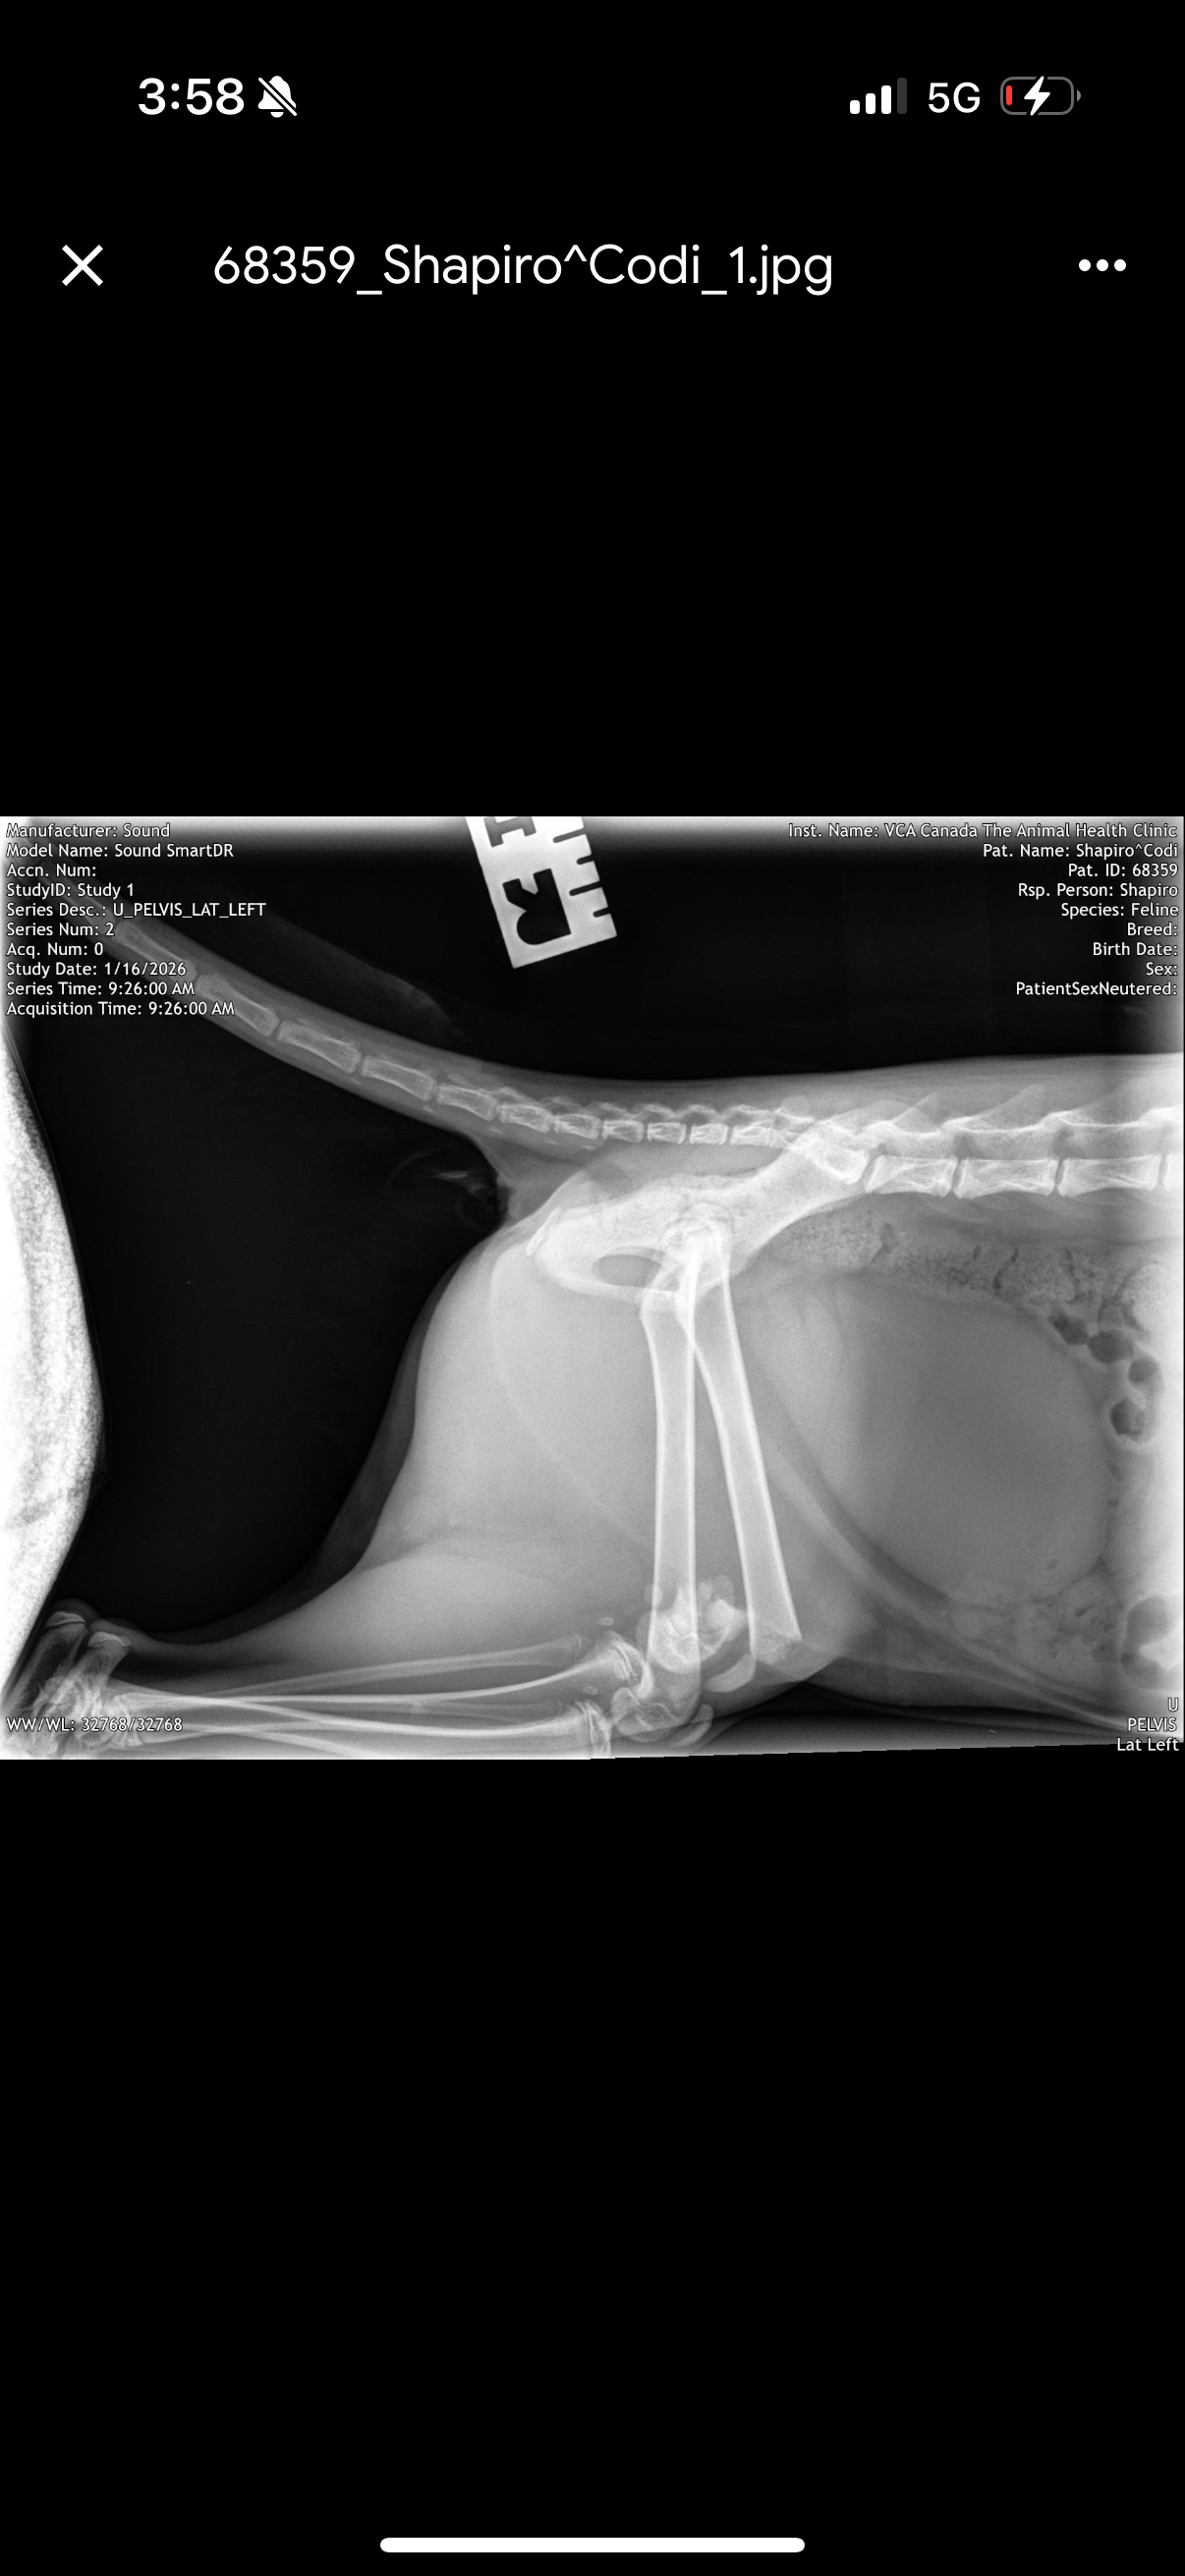

This is Codi, my 4.5–5-month-old kitten. She’s sweet, playful, and still just a baby. A sudden accident left her with a severe fracture to her left back leg, and she’s in pain but can absolutely recover with treatment.

Because I don’t have pet insurance, the emergency vet quoted up to $7,500 + tax for orthopedic surgery — a cost I simply cannot afford. I live in Montreal and am actively pursuing lower-cost options, and discussing hind-leg amputation as a last resort, which is a humane and successful option for many cats. Even these options still cost thousands of dollars, and time is critical.